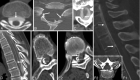

Despite extensive imaging, a source of bleeding is often not evident during the evaluation of patients with superficial siderosis (SS) of the central nervous system. An intraspinal fluid-filled collection of variable dimensions is frequently seen on spine MR imaging in patients with idiopathic SS. A similar finding has also been reported in patients with craniospinal hypotension. This review discusses the role of multitechnique imaging in the work-up of patients with SS and focuses on recent developments.